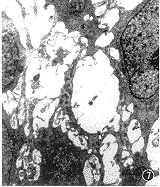

第1次冷冻后上皮细胞有明暗两种形态,明细胞核淡染,胞质空,细胞器变性重,可见许多大泡形成(图7)。暗细胞电子密度高,细胞器完整。上皮间有较多淋巴细胞浸润。

图7 第一次冷冻后鼻粘膜透射电镜图像,上皮间可见较多的大泡间隙(*)标尺=1 μm